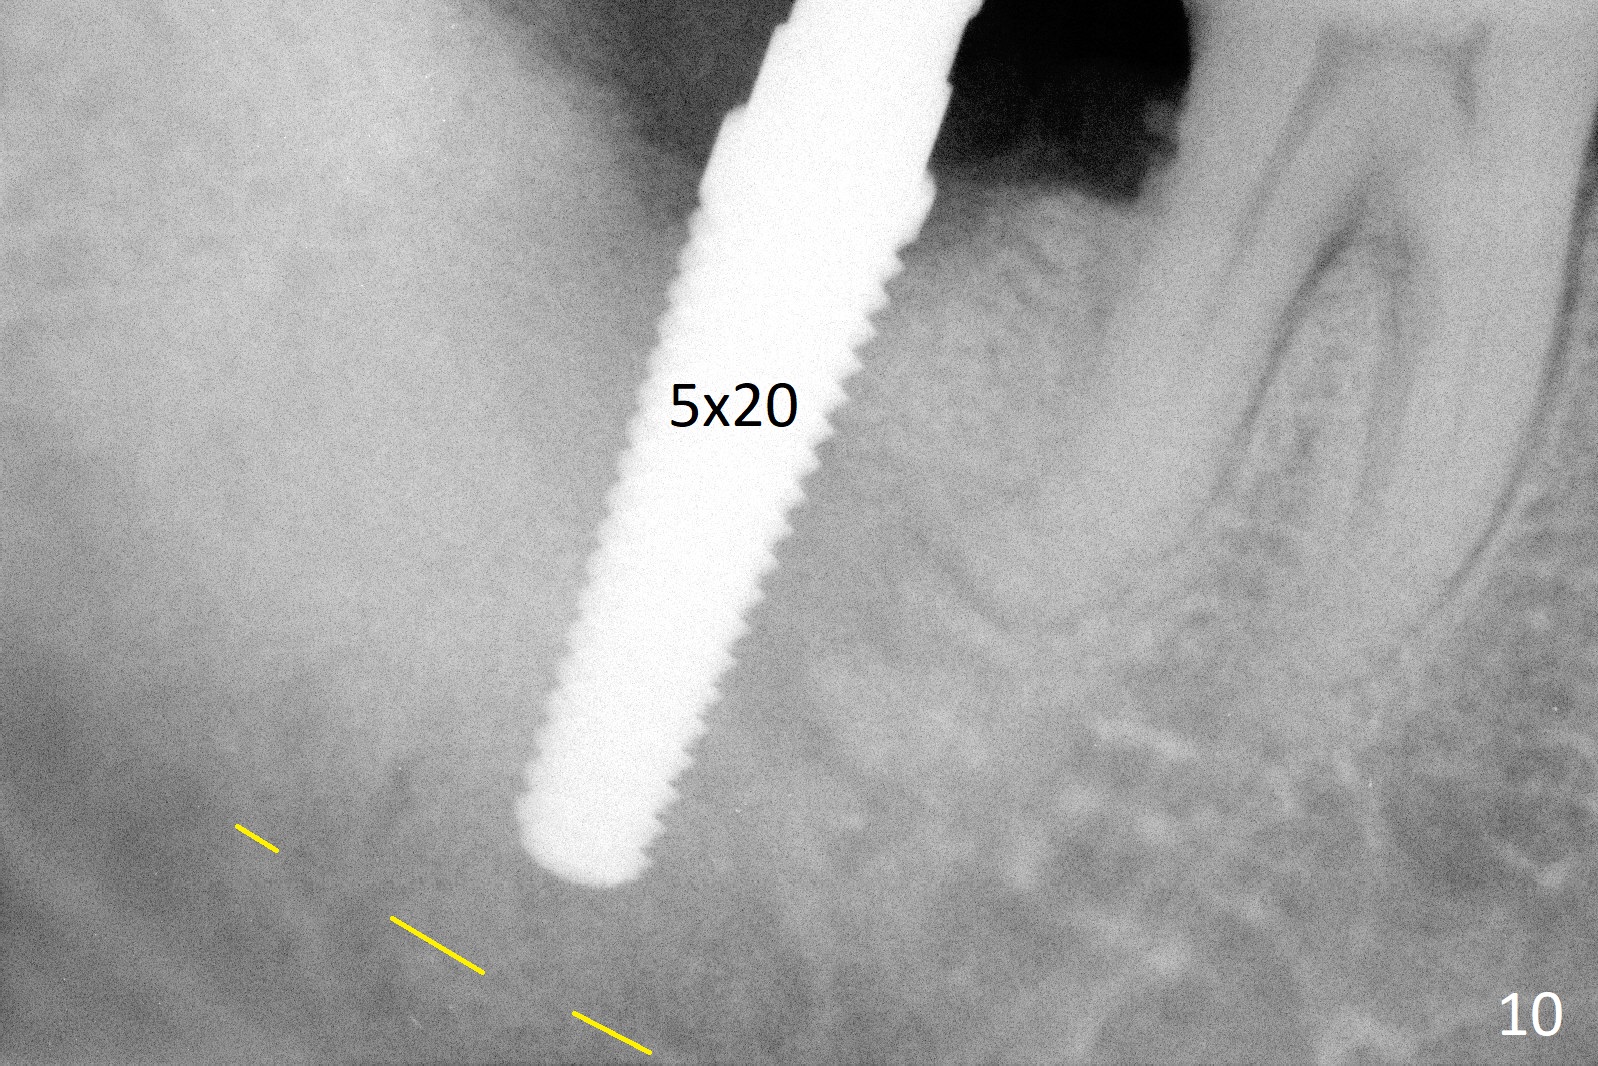

A 50-year-old man, a smoker, presents to clinic with pain of the tooth #15 with apparently occlusal trauma (Fig.1). Two years and three months after #15 extraction, he returns for #31 extraction (Fig.2) and socket preservation (Fig.3). The socket depth is 17 mm along the long axis of the socket 2.5 months post extraction (Fig.4, gingival level). Initial osteotomy is created in the mesial slope of the socket for 14 mm (Fig.5). After sequential osteotomy, a 6x17 mm tap is seated shallower (Fig.6) than the 2 mm drill (Fig.5). Following further osteotomy, a 7x14 mm implant is seated incompletely (Fig.7), which was not found intraop. The implant becomes loose with purulent discharge 19 days postop. The patient returns for 2nd placement 2 months post implant removal (Fig.8). Osteotomy is created probably in the mesial slope with 17 mm (bone level, Fig.9). After insertion of 5 (Fig.10) and 6 (Fig.11) x20 mm taps (tissue level), a 6x20 mm tissue-level implant is placed with clearance from the Inferior Alveolar Canal (Fig.12 yellow dashed line). The implant is restored 8.5 months postop (Fig.13) without bonding 5 mm 0 degree unipost. The crown dislodges 4 months post permanent cementation. Still the patient complains of small crown without occlusal contact. Impression is taken for a new normal-sized crown. The new crown becomes loose 1 year 9 months post cementation (Fig.14). The teeth #14 and 15 remain unrestored.